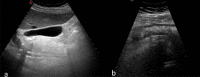

Diverticular disease is a common disorder and its incidence increases with ageing. Pathophysiology is multifactorial. Lifestyle, including smoking, alcohol intake, decreased dietary fibres and lack of physical activity, plays a predominant role. Genetics seems also to contribute specifically for right-sided diverticular disease (RSD). The majority of the patients with diverticular disease are asymptomatic. Diverticulitis is the inflammation of the diverticula usually presenting with abdominal pain associated to nausea, vomiting, rectal bleeding, diarrhoea and fever. When the inflammation process affects the diverticula in the ascending colon, the condition represents a clinical challenge as it can be easily misdiagnosed with other acute abdominal emergencies. We reported a case of a 70-year-old female who presented to our Emergency Department (ED) with right upper quadrant pain and an initial clinical suspicion of cholecystitis. Ultrasound (US) and Computed Tomography (CT) demonstrated an anatomical variation of the sigmoid colon diverticulitis. This clinical report demonstrates that ultrasound plays a relevant part as first-step approach to the acute abdominal conditions and its accuracy increases together with other diagnostic tools such as Computer Tomography.